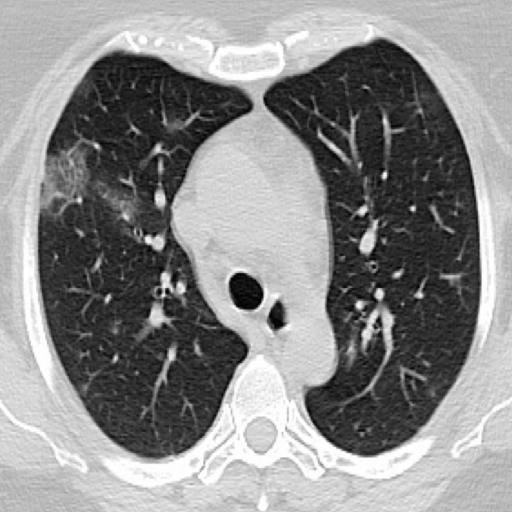

The extent to which the raw medical data is protected is shown in the following Figures. Figure 2 shows the degree to which the original COVID-19 CT scan is distorted after passing through one hidden layer of each hospital. Figure 2 (a) is the original CT scan of a COVID-19 patient. Figure 2 (b) is the highly deformed image of image (a) after it undergoes the first hidden layer. Each hospital will produce an image like Figure 2 (b). All of these feature maps are concatenated and communicated to the server where it then trains the deep neural network.

![]() |

| (a) | (b) |